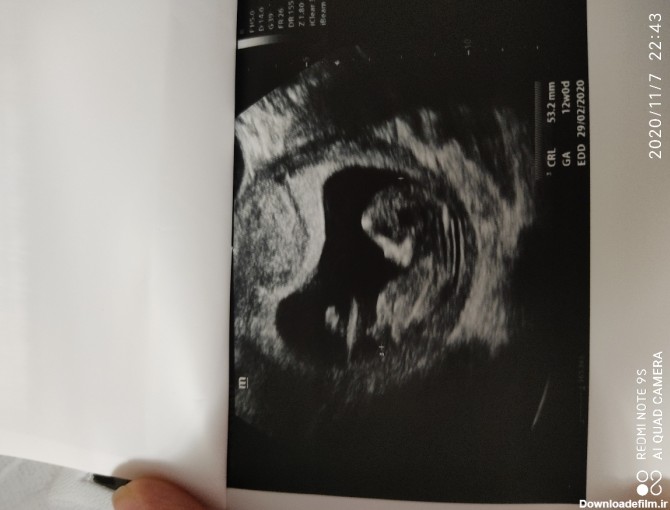

خانوم خوشگلا بیاین بگین امسال کسی بوده که سونوntبدین بعد احتمال بدن بچشون دختر هست ولی بعدش پسر باشه؟!من استرس دارم اگر کسی هست سونو من شبیه سونوی خودشه بگه جنس

مامانایی که بلدن بیان ببینن از رو عکس میتونن تشخیص بدن جنسیت نی نی مو وای میشه منم بذارم مال منم بگید؟

دخترهاز جمجمش حدس زدم بچه ها رفتم غربالگری اول ان تی گفت احتمالا پسره به نظر شما چیه؟ چند درصد احتمال داره درست باشه؟

خانومای باتجربه بیاین بگین nt نی نی من دخمله یا پسر

سلام بچه ها کی بلده تشخیص جنسیت بده از عکس سونو ان تی؟ لطفا بگید جنسیت بچه ی من چیه

سلام دیروز رفتم سونو ان تی از بس بدقلقی کرد سه بار سونو شدم تا تونست ان تی رو بگیره .دیگه ب جنسیت نرسیدشما بلدین از روی عکس ان تی تشخیص بدین؟